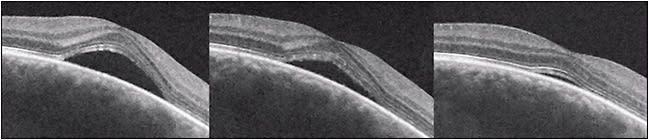

Several active treatment approaches to CSC have been found to be beneficial. Photodynamic therapy with verteporfin (Visudyne) reduces choroidal hyperpermeability, decreases choroidal vascular congestion and thickness, and is effective in the treatment of chronic CSC (Figure 5). Due to concerns of induction of CNV with full (standard) fluence PDT, low-fluence PDT was attempted and was shown to be beneficial.30-35